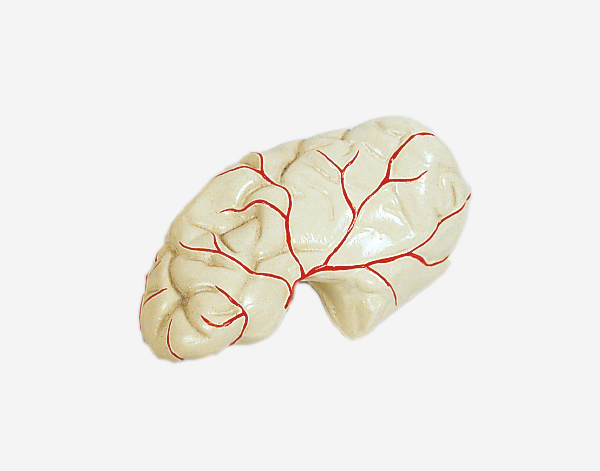

Human Brain With Arteries

Model of Human Brain With Arteries

This model facilitates the medical students to get a correct understanding of the external features of the brain and its arte

rial supply as a whole,as well as the relations between their component portions.External features of the brain:cerebral

hemisphere,brain stem,cerebellum.The arterial supply of the bra inaources,vertebral,internal carotid arteries,arteria supply of the

cerebellum and cerebrum.Made of PVC and can be separated into 7parts,on base.Size(cm):17x17x13